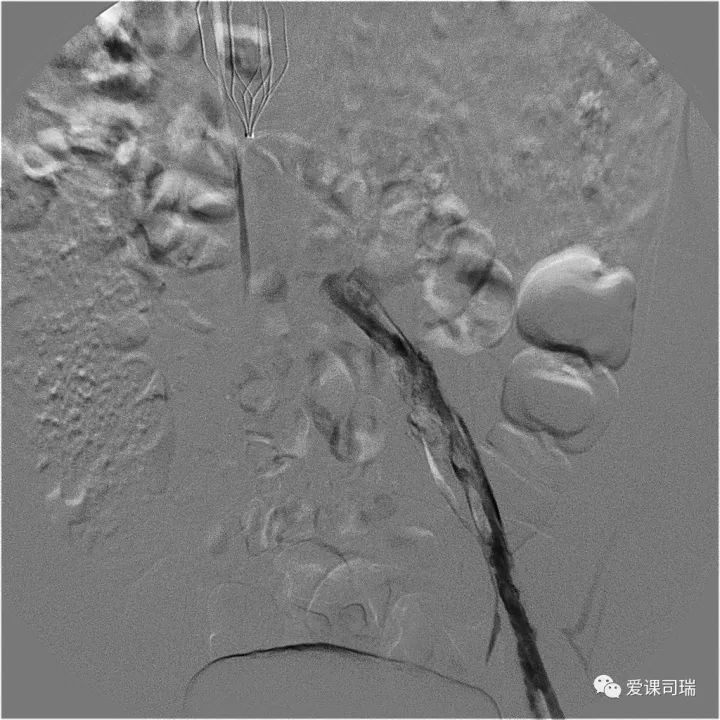

下肢深静脉急性血栓形成

静脉造影提示髂静脉血栓形成后闭塞